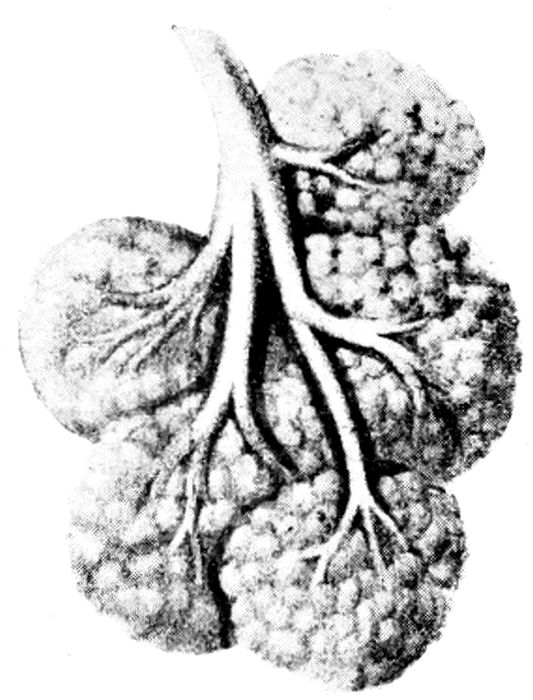

Fig. 17.—Maternal surface of the placenta and membranes. The cord protrudes from the cavity which held the fœtus. (Edgar.)

The Placenta.—The placenta or “after-birth” is an

oval or circular somewhat flattened disc, six to ten inches

in diameter, and three-quarters to one and one-half inches

thick. It weighs about a pound and a half. It is the organ

of respiration and nutrition for the fœtus.

Fig. 18.—Fœtal surface of human placenta. (Eden.)

It is formed about the third month outside the membranes

covering the child and is more or less loosely attached

to the uterine wall. The umbilical cord is attached

to its fœtal surface, inside the ovum. Like a flat

sponge it takes oxygen, blood, and the nourishing fluids

from the blood vessels in the uterine wall, carries them to

the child by means of the umbilical vein, and carries back

43the carbonized blood and waste products by the umbilical

arteries to the placenta, and there returns them to

the maternal blood for disposal. The blood of the veins

is bright red, and of the arteries, dark and turbid.